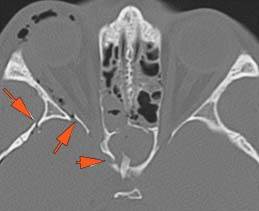

The zygomatic arch is fractured.

There is entrapment of the muscles of mastication by fractures of the coronoid process and/or zygomatic arch.

There is bony injury of the body, alveolar ridge, premaxilla, the infraorbital rim, the palatine or the frontal process of the maxillary bones on either side.

The pterygoid processes of the sphenoid bone are fractured.